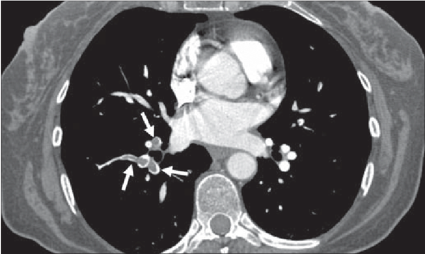

Lungeemboli:

- Embolier (mørke) omsluttet af blod (lyst)

Diagnose?

Lungeemboli